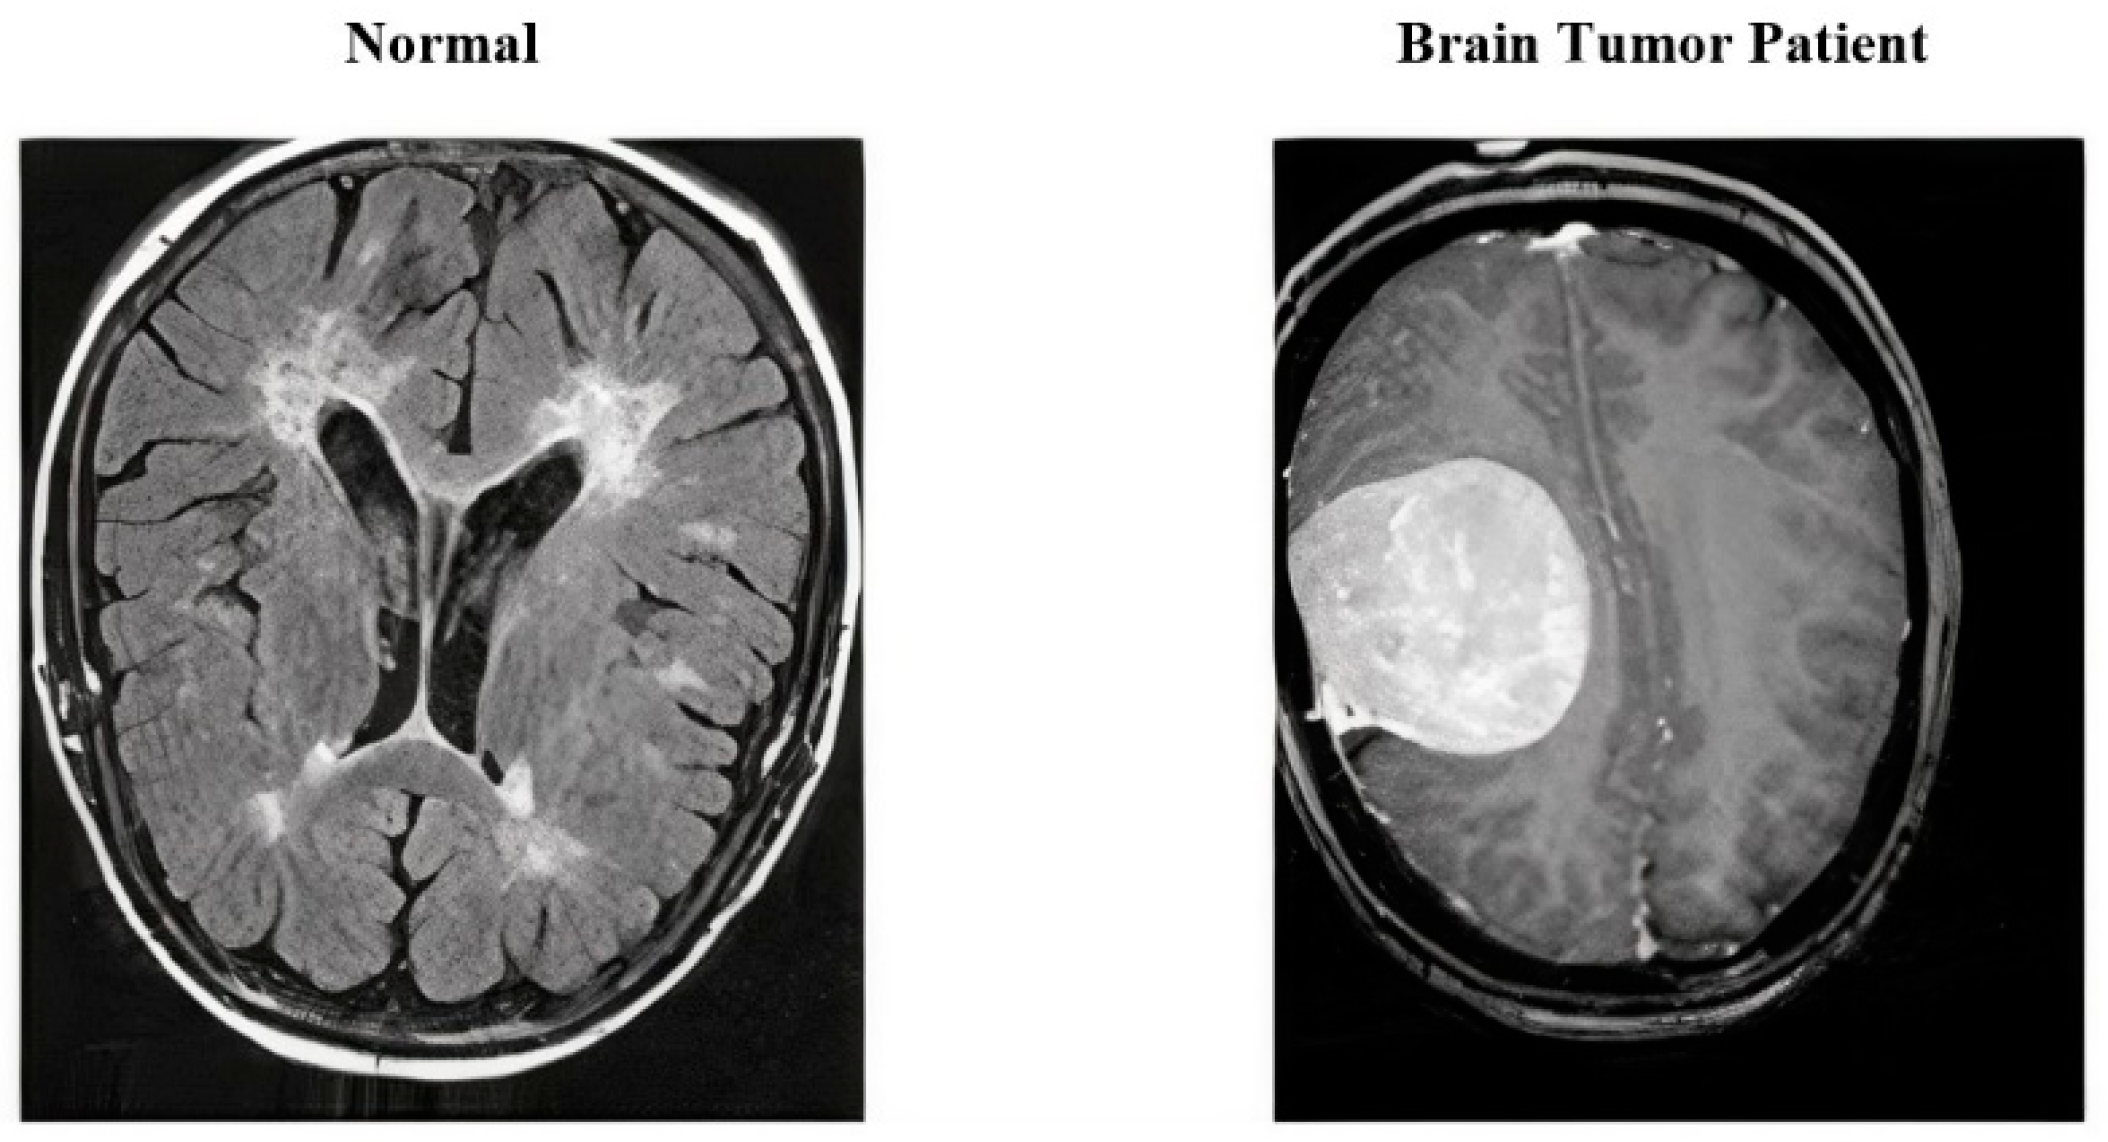

3.1. Dataset Used